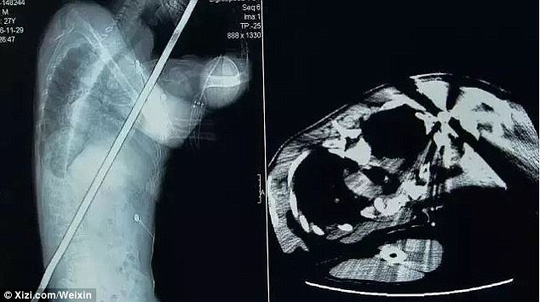

Thanh sắt – dài khoảng 2 m – đâm xuyên qua người A Feng, 28 tuổi, làm thợ xây công trình khiến anh phải nhập viện. May mắn vết thương không đe dọa đến tính mạng.

Một số hình ảnh đăng tải trên kênh GDTV làm người xem ớn lạnh vì chúng không khác gì trong các bộ phim kinh dị. Theo kênh truyền hình này, thanh sắt rớt xuống từ tầng thứ 7 của tòa nhà đang xây dựng. Sau tai nạn, A Feng được chuyển tới bệnh viện chuyên khoa ở TP Huệ Châu.

Que sắt đâm xuyên qua người A Feng. Ảnh: GDTV

Các bác sĩ mất 2 giờ để làm phẫu thuật loại bỏ thanh sắt ra khỏi người bệnh nhân. Bác sĩ Yang Wendong cho biết họ không thể đặt A Feng nằm như bình thường vì que sắt quá dài. Trước khi phẫu thuật, lính cứu hỏa được gọi tới để cắt thanh sắt xuống còn gần 1 m.

Sau khi kiểm tra, nhóm phẫu thuật sửng sốt vì thanh sắt đâm xuyên qua bụng, phổi, gan và thận của nạn nhân. Tuy nhiên, do nó không xuyên qua các động mạch chủ cũng như chỉ làm tổn thương bề mặt phổi nên A Feng không tử vong.

Các bác sĩ đang lấy que sắt khỏi người bệnh nhân. Ảnh: WEIXIN

Ảnh: WEIXIN

Ban đầu, các bác sĩ chỉ mất 2-3 phút để rút thanh sắt từ vai bệnh nhân ra. Sau đó, họ tiến hành phẫu thuật ghép nối những bộ phận cơ thể bị ảnh hưởng.